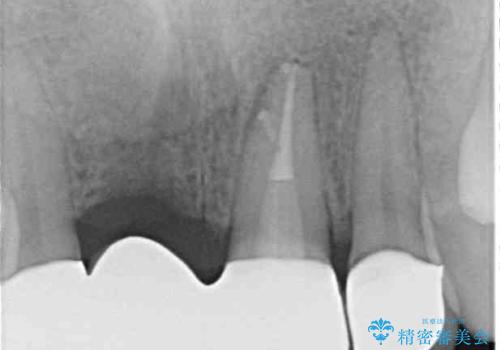

当初のレントゲン写真では根尖部に骨透過像が認められた両サイドの2歯は、歯髄の正常な反応が認められたためそのまま保存し、左側前歯は歯髄が失活していたため根管治療を行うこととしました。

抜歯後の欠損部はブリッジにて補綴治療を行うこととしました。

事故直後のレントゲン写真では全ての歯の根尖部に骨透過像が認められましたが、治療後には全ての透過像がなくなっていました。

診断に2-3ヶ月かかりましたが、的確に診断を行うことができました。